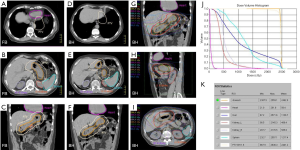

For patients presenting with stage IE or stage IIE disease, RT is recommended if the volume of lung exposed to radiation is not excessively large. Pre-RT assessment of pulmonary and cardiac function is important, and should include clinical evaluation, spirometry and diffusion capacity, and cardiac ejection fraction. The target volume encompasses the gross disease with a margin taking account of organ motion due to the respiratory cycle (Figure 6A). Established methods of motion management (e.g., DIBH) should be used whenever feasible. A RT dose of 24–30 Gy given in 1.5–2.0 Gy fractions over 2 to 3 weeks is prescribed (Figure 6B, C and D). As the lung tissue has limited tolerance to radiation (79,80), large target volumes result in a high risk of radiation pneumonitis and later pulmonary fibrosis with functional impairment. Therefore, if the tumor is bulky, or has significant pleural extension or malignant effusion, or if multiple lung nodules are present, conventional RT fractionation should not be used. Low dose RT with 2×2 Gy regimen can be very effective for local control (11). Otherwise, for more extensive disease chemotherapy is recommended. Lung tissue exposed to a dose of 30 Gy given in 2 Gy fractions or less have an approximately 40–50% chance of manifesting visible changes of pneumonitis on a CT scan (80). Factors that affect this risk include the volume of lung tissue irradiated, and the dose/fraction (81). The presence of RT changes in the lung can make response assessment difficult if residual treatment related abnormalities persist. For patients with small MALT lymphomas treated with complete surgical excision confirmed pathologically, RT may be unnecessary. If resection margins are positive, postoperative RT can be considered.